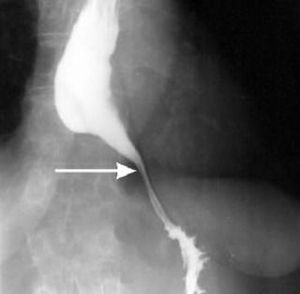

This barium swallow shows "Bird's Beak" appearence which is a characteristic of Achalasia.Achalasia is the most common motility disorder, it affects the distal part of esophagus. It results from the degeneration of myentric plexus with an autoimmune reaction leading to loss of nitric oxide producing neurons which results in failure of lower esophageal sphincter relaxation. Treatment of Achalasia can be medical treatment by using nifedipine, long acting nitrates, or botulinum toxin injection, and the Surgical treatment is endoscopic balloon diltation of lower esophageal sphincter.